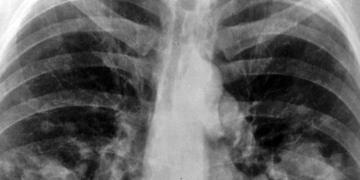

25 bin’den fazla bireyi kapsayan yedi araştırmanın toplu analizi sonucunda, akciğer kanseri gelişimi riski ve birtakım basit solunumsal hastalıklar arasında bazı bağlantılar bulundu.